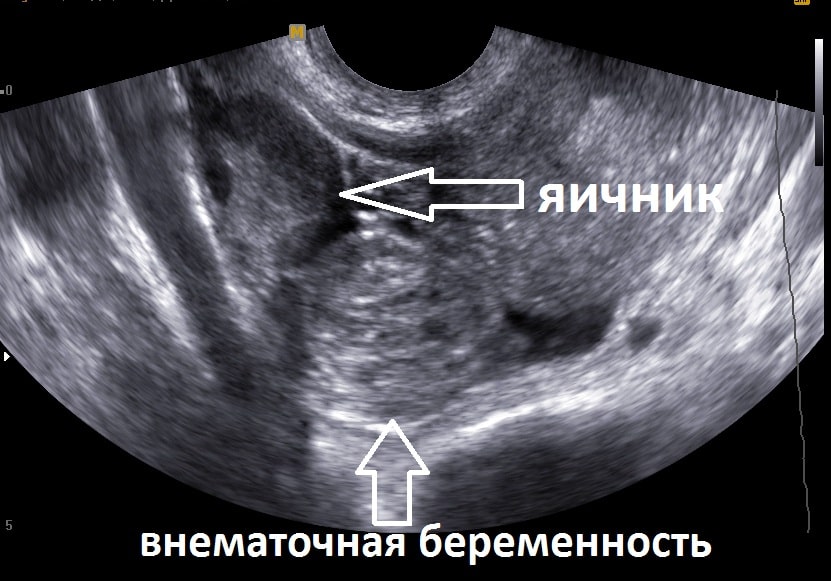

В случае медицинских показаний может потребоваться удаление одной или обеих маточных труб. Потеря даже одной трубы несет последствия. Прежде всего, отсутствие одной из труб снижает вероятность естественного зачатия почти вдвое, так как обычно яйцеклетка выходит из них поочередно каждый месяц. Таким образом, выход яйцеклетки происходит теперь гораздо реже. Если в оставшейся трубе присутствуют образования, такие как спайки, то даже при успешном оплодотворении существует высокий риск развития внематочной беременности. Удаление одной из труб увеличивает вероятность внематочной беременности, даже если вторая труба на месте.